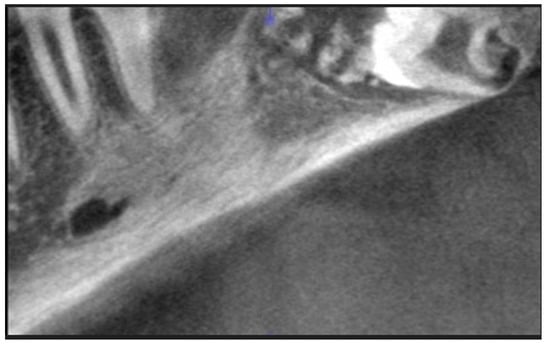

Treatment Possibilities in Mandibular Defect Reconstruction Based on Ameloblastic Fibro-Odontoma Treatment—Does Small Bone Defects Heal without Bone Grafting?

2. Case Report Presentation